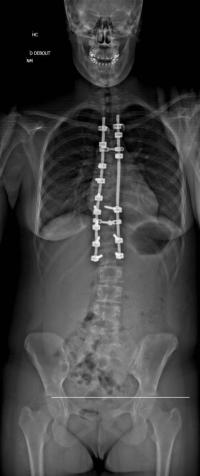

Images de scolioses opérées 16 janvier 202418 janvier 2023 par Damien Scoliose Thoracique 2 Scoliose thoracique Droite - cliché pré-opératoire de Face Scoliose thoracique Droite - cliché pré-opératoire de Profil Scoliose thoracique Droite - cliché post-opératoire de Face Scoliose thoracique Droite - cliché post-opératoire de Profil